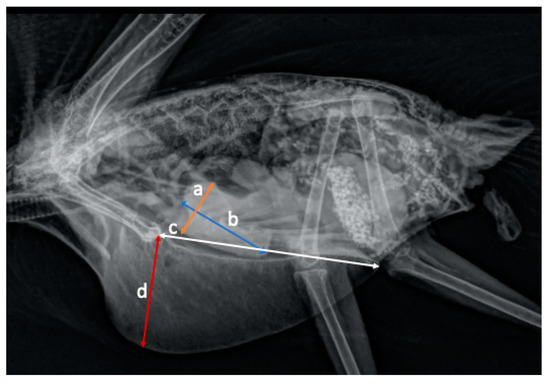

Radiographic Measurements of the Cardiac Silhouette and Comparison with Other Radiographic Landmarks in Wild Galahs (Eolophus roseicapilla)

by Petra Schnitzer, Shivananden Sawmy and Lorenzo Crosta

Animals 2021, 11(3), 587; https://doi.org/10.3390/ani11030587 - 24 Feb 2021

Background: Part of the diagnostic workup for cardiac diseases is radiographic imaging. To determine an enlarged heart, species-specific reference values are necessary. Wild birds are rarely diagnosed with cardiac disease, and only a few studies have been done to investigate the cardiac silhouette [...] Read more.

Background: Part of the diagnostic workup for cardiac diseases is radiographic imaging. To determine an enlarged heart, species-specific reference values are necessary. Wild birds are rarely diagnosed with cardiac disease, and only a few studies have been done to investigate the cardiac silhouette in wild birds. Methods: In this retrospective study, the cardiac silhouette of 36 wild galahs, presented at the hospital, was investigated in relation to other anatomic landmarks like the thoracic width, clavicula width, synsacrum width, distance between the third and fourth rib, distance of the clavicula, and length and height of the sternum using a digital DICOM viewer. Results: The cardiac width was significant compared to the thoracic width with a minimum to maximum of 50 to 65%. The cardiac width compared with the coracoid width also showed significant results with a minimum to maximum range of 570 to 743%. A significant correlation was found between the weight and the cardiac width and length. Conclusion: The cardiac silhouette in wild galahs is easily measured in both radiographic views, and the heart size can be compared to other anatomical landmarks. Full article